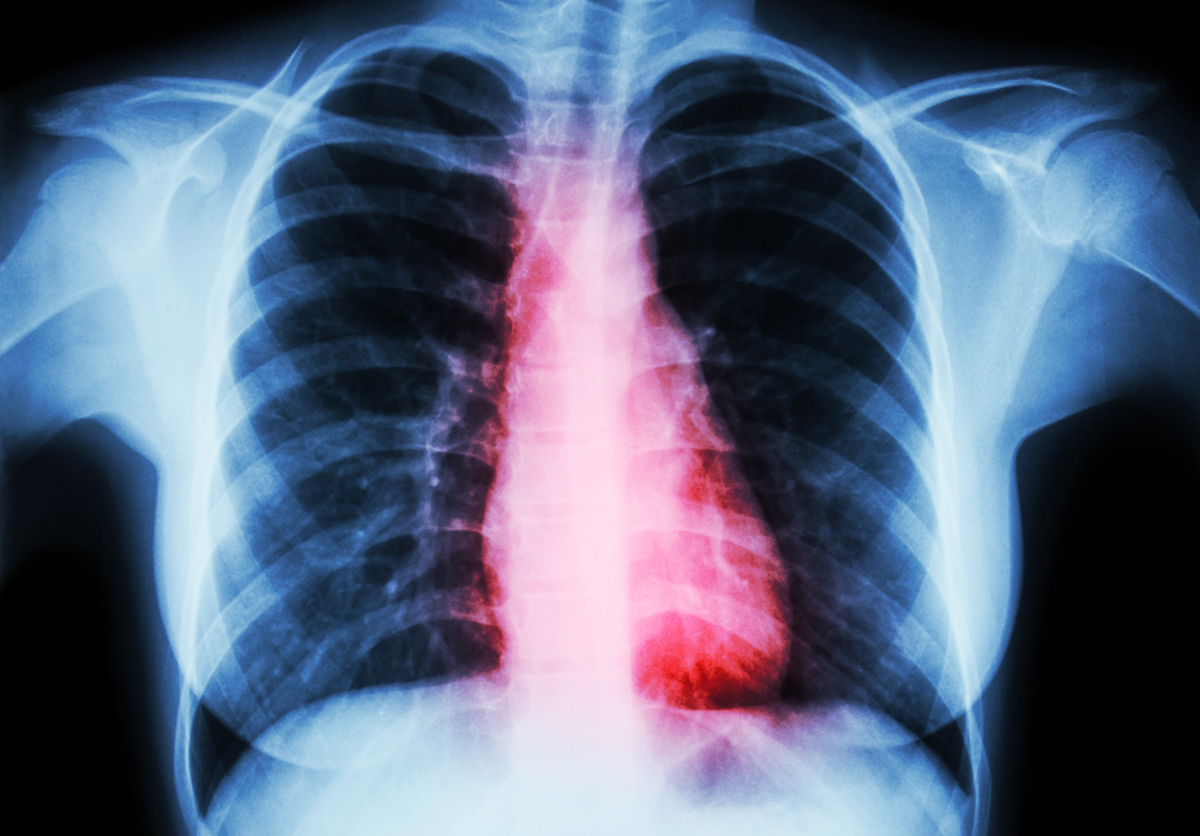

Heart disease ( Film chest x-ray of woman with heart disease )